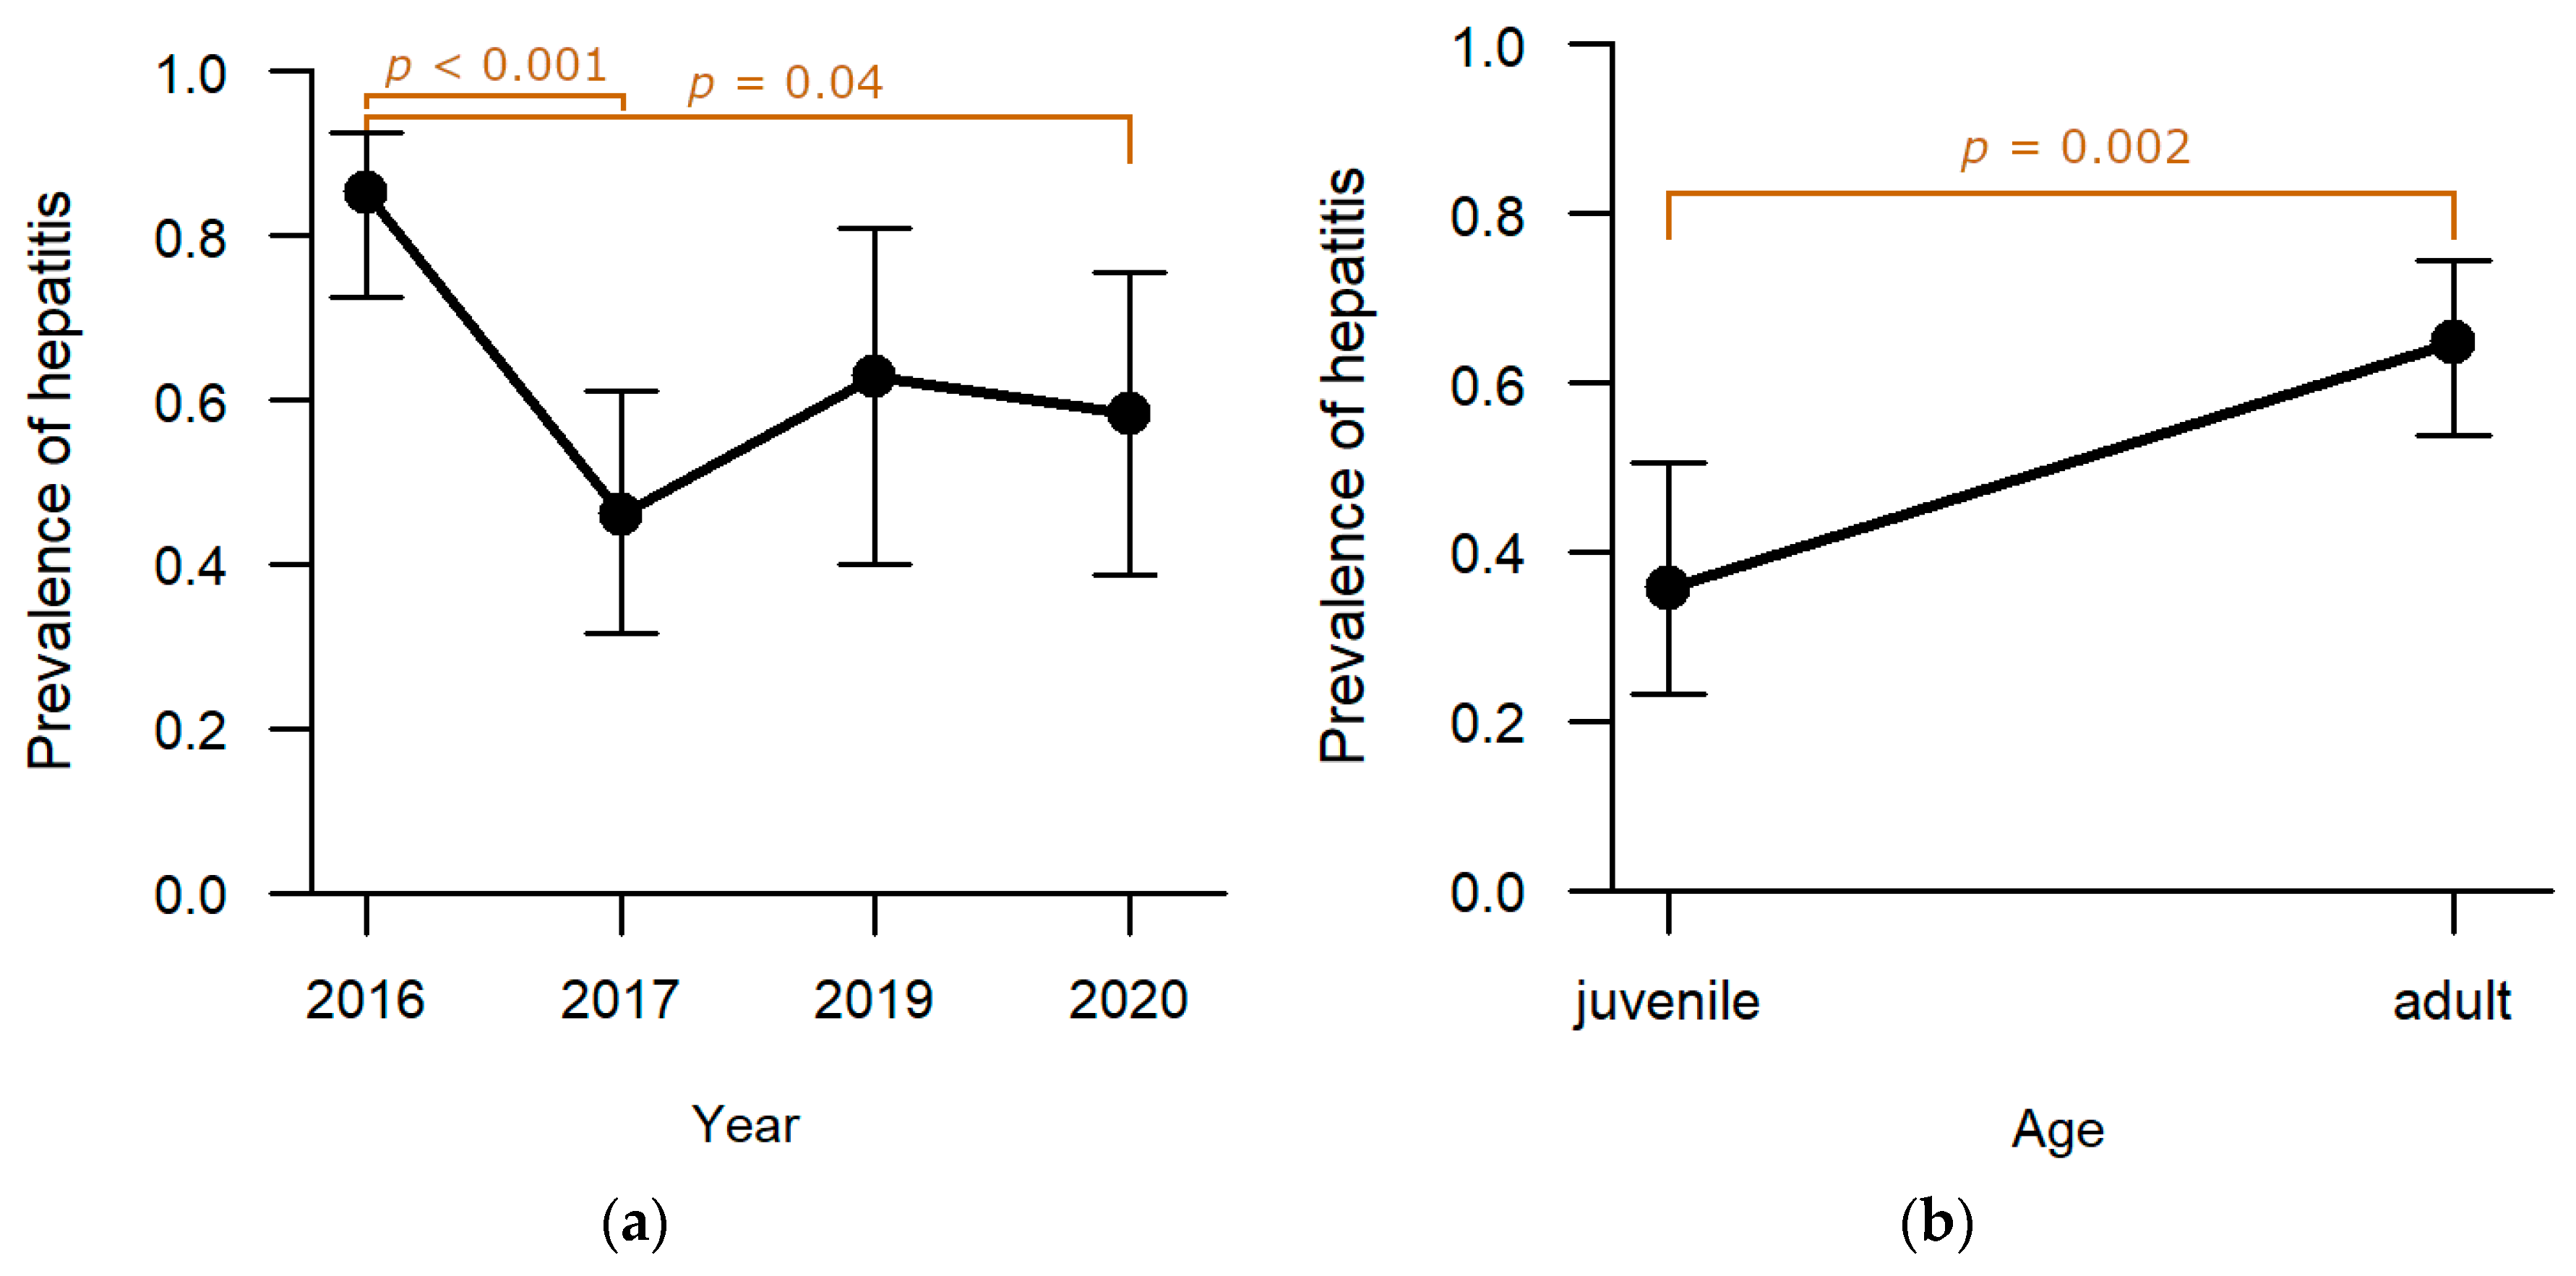

Liver: Among the six pathomorphological findings analysed in depth, hepatitis was the second most common and was observed in 55.5% (n = 86) of the studied individuals. Sampling year (

p = 0.0002;

Table S1) and age (

p = 0.002;

Table S1) proved to have a significant effect on the presence of hepatitis whereas hunting ground and sex did not reveal a significant effect. Highest levels of hepatitis were observed in 2016 (

Figure 3a). Post-hoc analyses confirmed that the drop to lower levels in 2017 (

p = 0.0003;

Table S2) and 2020 (

p = 0.041;

Table S2) was significant. Adults were significantly more frequently affected than juveniles (

p = 0.002;

Table S1;

Figure 3b).